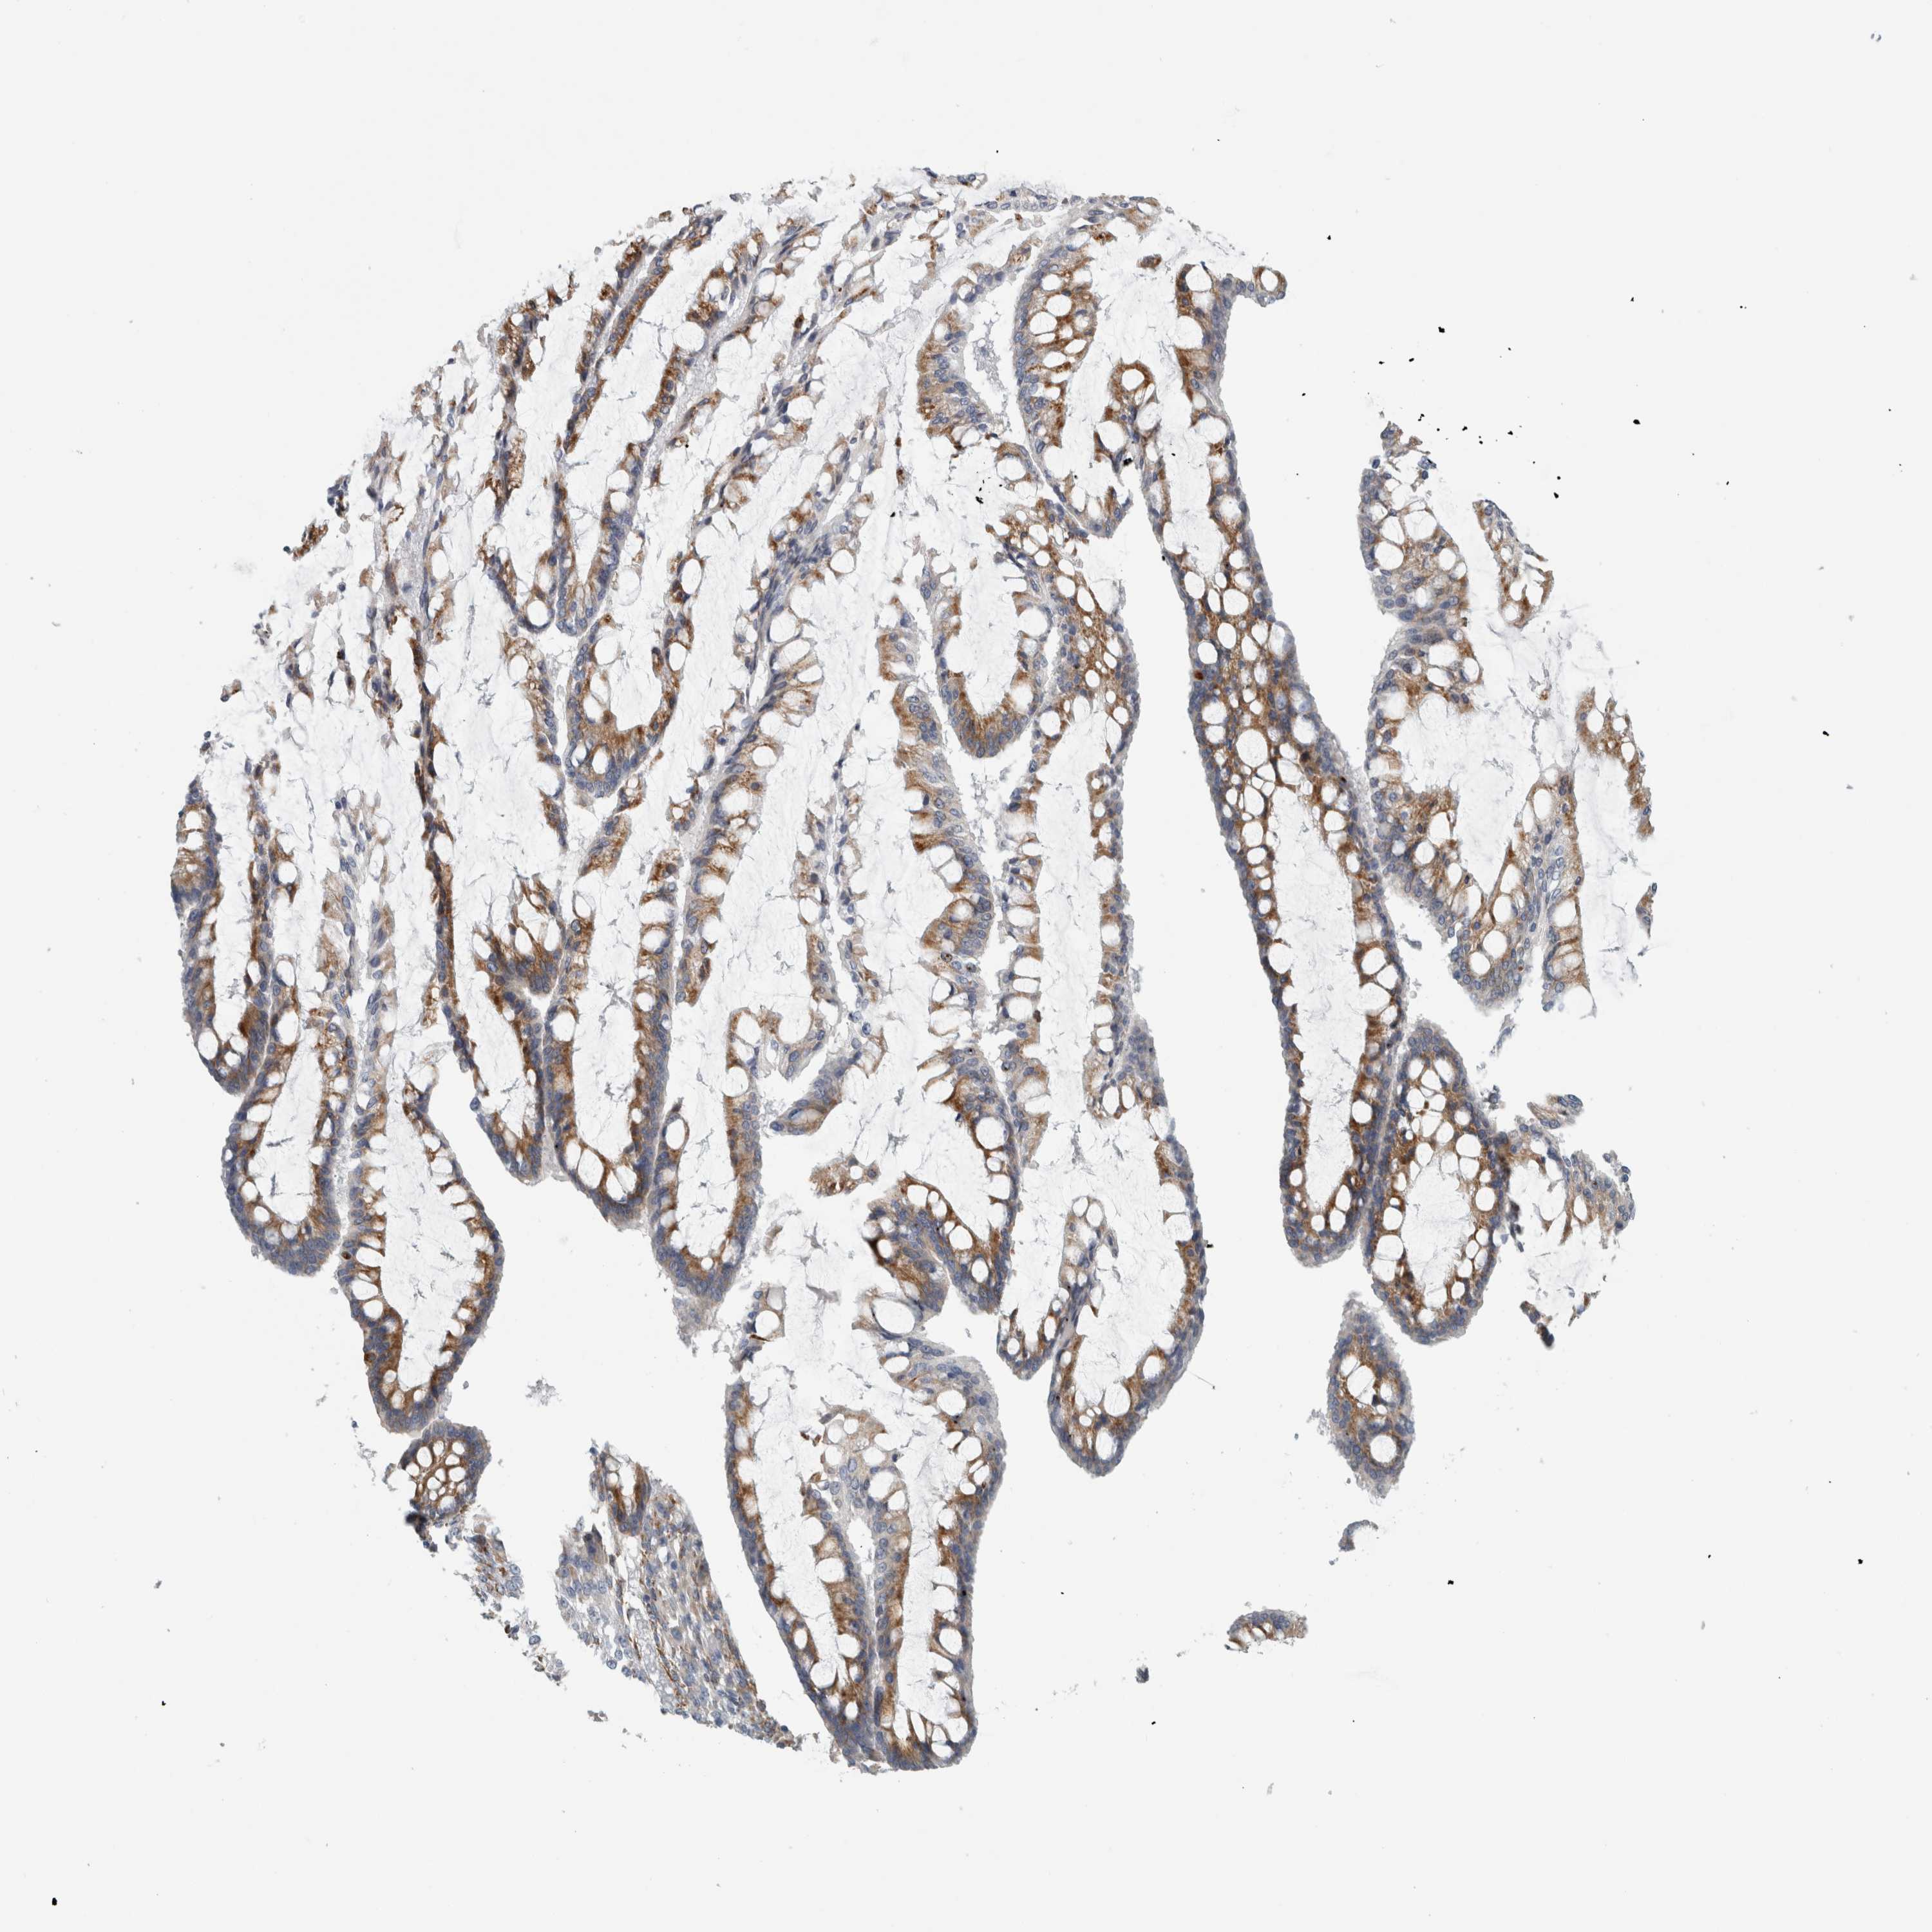

OVARIAN CANCER - Protein expressioni

A mouse-over function shows sample information and annotation data. Click on an image to view it in a full screen mode. Samples can be filtered based on level of antibody staining by selecting one or several of the following categories: high, medium, low and not detected. The assay and annotation is described here.

Note that samples used for immunohistochemistry by the Human Protein Atlas do not correspond to samples in the TCGA dataset.

Antibody stainingi

Antibody staining in the annotated cell types in the current human tissue is reported as not detected, low, medium, or high, based on conventional immunohistochemistry profiling in selected tissues. This score is based on the combination of the staining intensity and fraction of stained cells.

Each image is clickable and will lead to virtual microscopy that enables deeper exploration of all samples and also displays staining intensity scores, fraction scores and subcellular localization as well as patient and tissue information for each sample.

Antibody HPA024298

Staining

High

Medium

Low

Not detected

Intensity

Strong

Moderate

Weak

Negative

Quantity

>75%

75%-25%

<25%

None

Location

Nuclear

Cytoplasmic/membranous

Cytoplasmic/membranous,nuclear

Cystadenocarcinoma, serous, NOS

Carcinoma, endometroid

Cystadenocarcinoma, mucinous, NOS

Carcinoma, NOS